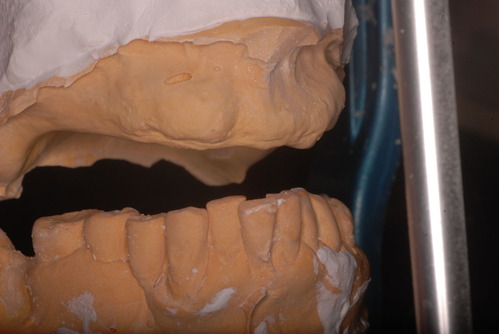

とりあえず、分析の為に修理した入れ歯を入れて下の歯と上の歯茎の出具合、人工の歯を並べる骨のトンガリ部分の位置関係を調べる為に、機械に付けて観察。

前歯のところの骨を少し削るとかしないと前突感は解消できないと分析できた。後は後方の入れ歯の位置をどこまで延ばすか調べるのです。

しかし、この位置の間違いの入れ歯が多くて殆ど吸着せずに脱落する入れ歯が多いのです。歯科医師が模型から作られた仮のプラスチックでその位置を口腔内で確認し、修正してからでないと前過ぎると落ちてしまい、奥に行きすぎると吐き気を催すのです。

位置としては、骨の触れる部分と軟組織(やわらかい部分)の境目が基本でここを試行錯誤で模型に印記し、その後方1~2mmまで模型を削り、実際のお口の中では軟組織に食い込むようにしなければ吸着せずに脱落するのです。

後は上の骨の最も出ている骨の部分と下の歯の位置関係を調べてどのような人工歯をどの位置に並べるかを考えるのです。